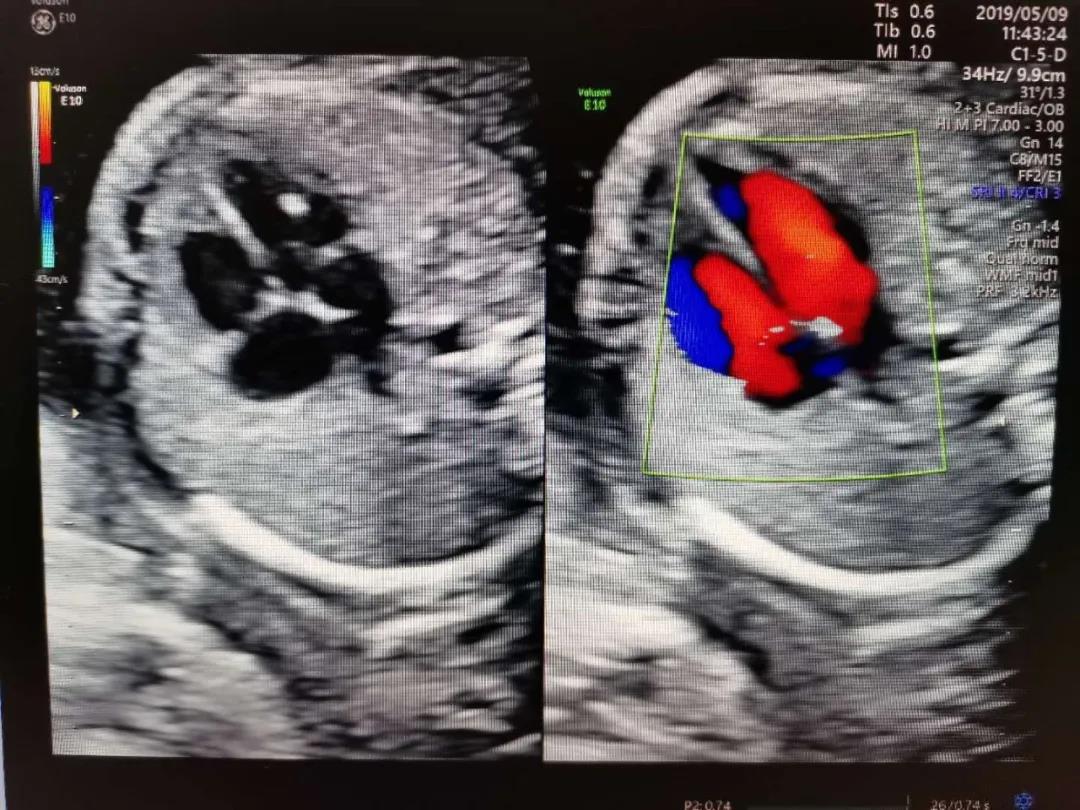

1.心脏强回声

心室强光点是孕期最为常见的强回声,这些孤立的强回声不会影响心功能,也不是胎儿心脏的结构异常的表现,一般孕晚期会消失,有时会追溯到新生儿期。其在正常胎儿中发生率在2%-5%。

宝妈们遇到这样的报告,如果染色体异常筛查低风险,我们可以选择乐观一些。但对本身存在染色体异常高风险的人群还是要更谨慎一些,要听听产科医生的意见。